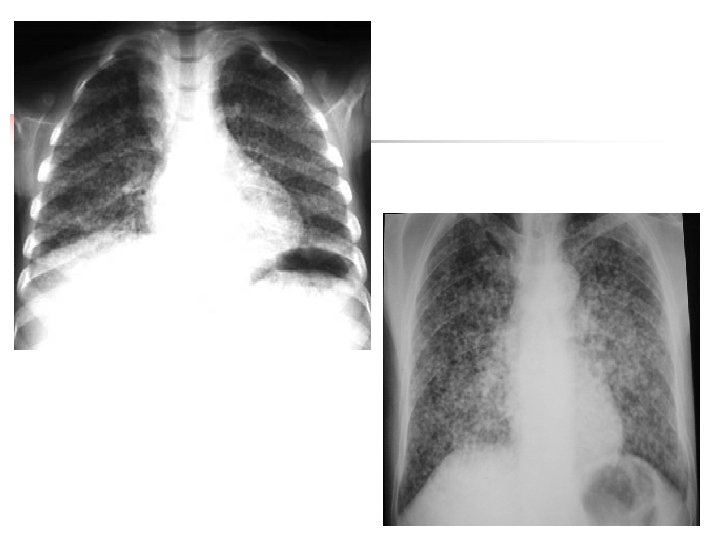

Radiographie standard Technique: Icidence de face en inspiration profonde ± profil. Clichés numérisés +++ n Limites: Superposition des plans. Qualité : mauvaise pénétration/cliché mal inspiré Peut étre normale au stade de début. n

Opacités linéaires septales Radiographie standard Visibilité anormale des septas interlobulaires épaissies n Lignes de Kerley A : Lignes longues + curvilignes de 3 -5 cm. Parties moyennes et supérieures des poumons (au dessus des hiles) n Lignes de Kerley B: +++ Courte de 1 -2 cm horizontal Lobe moyen et lingula, territoires antérieurs et externes (au dessous des hiles). n Lignes de Kerley C: Lignes entrecroisées : superposition des lignes A et B. Parties moyennes n Les lignes de Kerley D: Epaisses de 4 à 6 cm de long (partie antérieure des poumons)